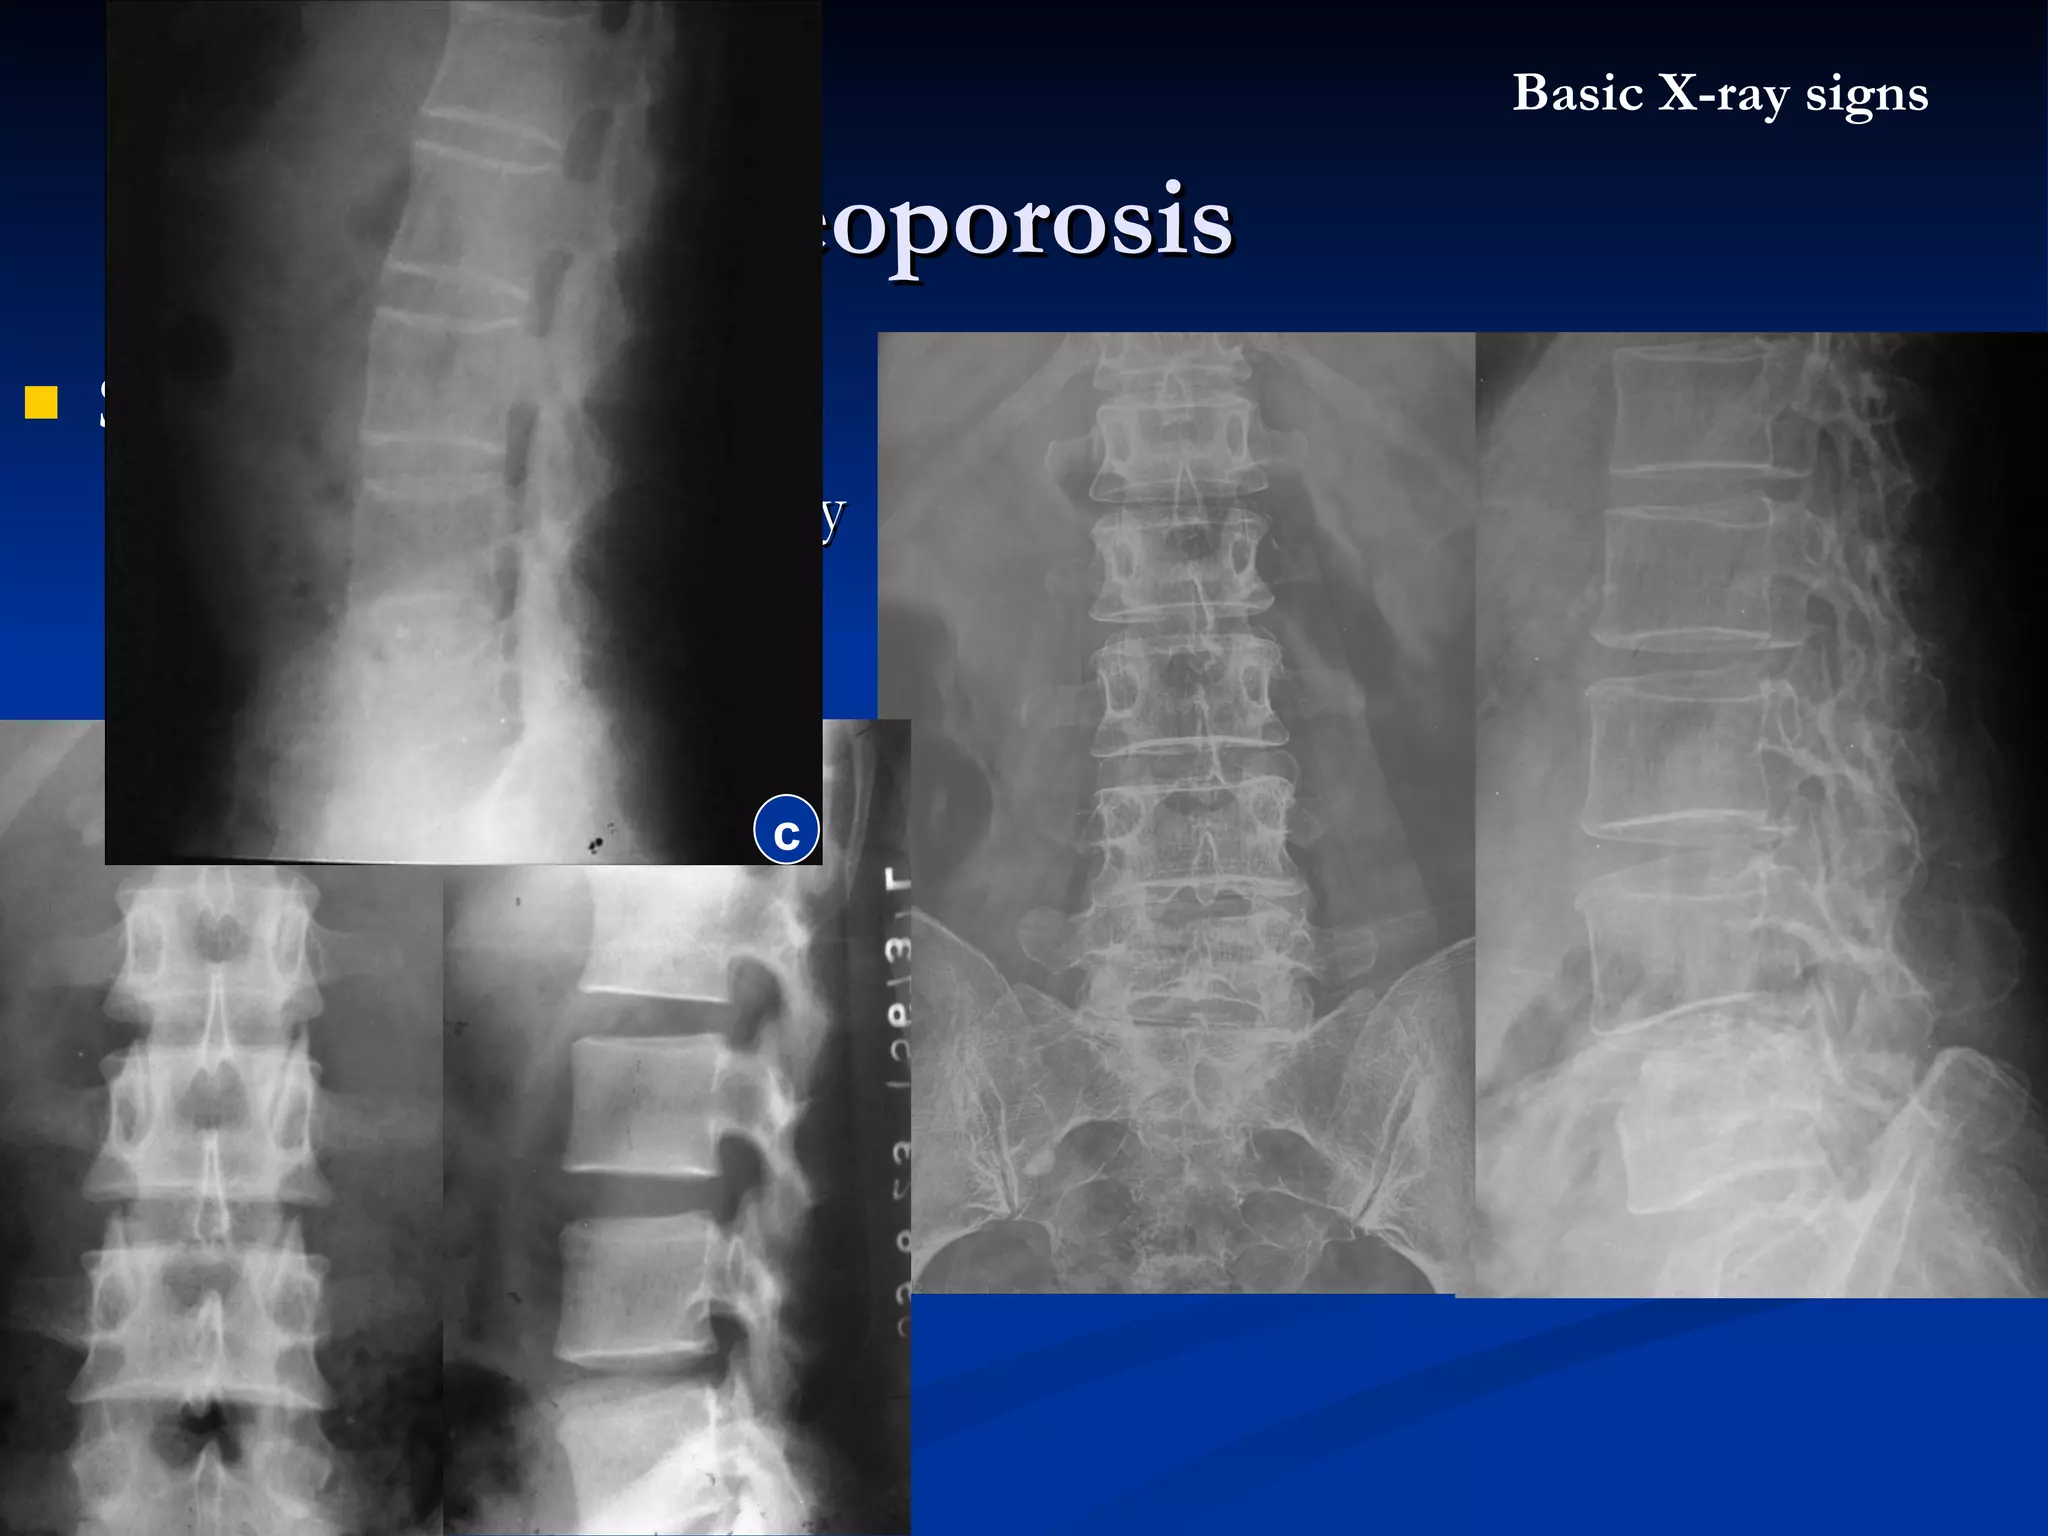

Osteoporosis Definition  : The bone matrix or osteoid specific deficiency Both of the organic material & calcium are decreased, but the ratio of them still normal X-ray appearance : Bone density decreased, local / general The cortex become thinner , the trabeculae become thin and decreased number   Pathological fracture Etiology  : Common  : elderly , immobilization Path : hormonal  / vitamine deficiency Basic X-ray signs

Spine oteoporosis Vertibral body deformity as  “ fish vertibral ” Bone density decreased Trabecula thinner Osteoporosis Basic X-ray signs normal c

Spine oteoporosis Vertibralbody deformity as “ fish vertibral ” Bone density decreased Trabecula thinner Osteoporosis Basic X-ray signs normal c